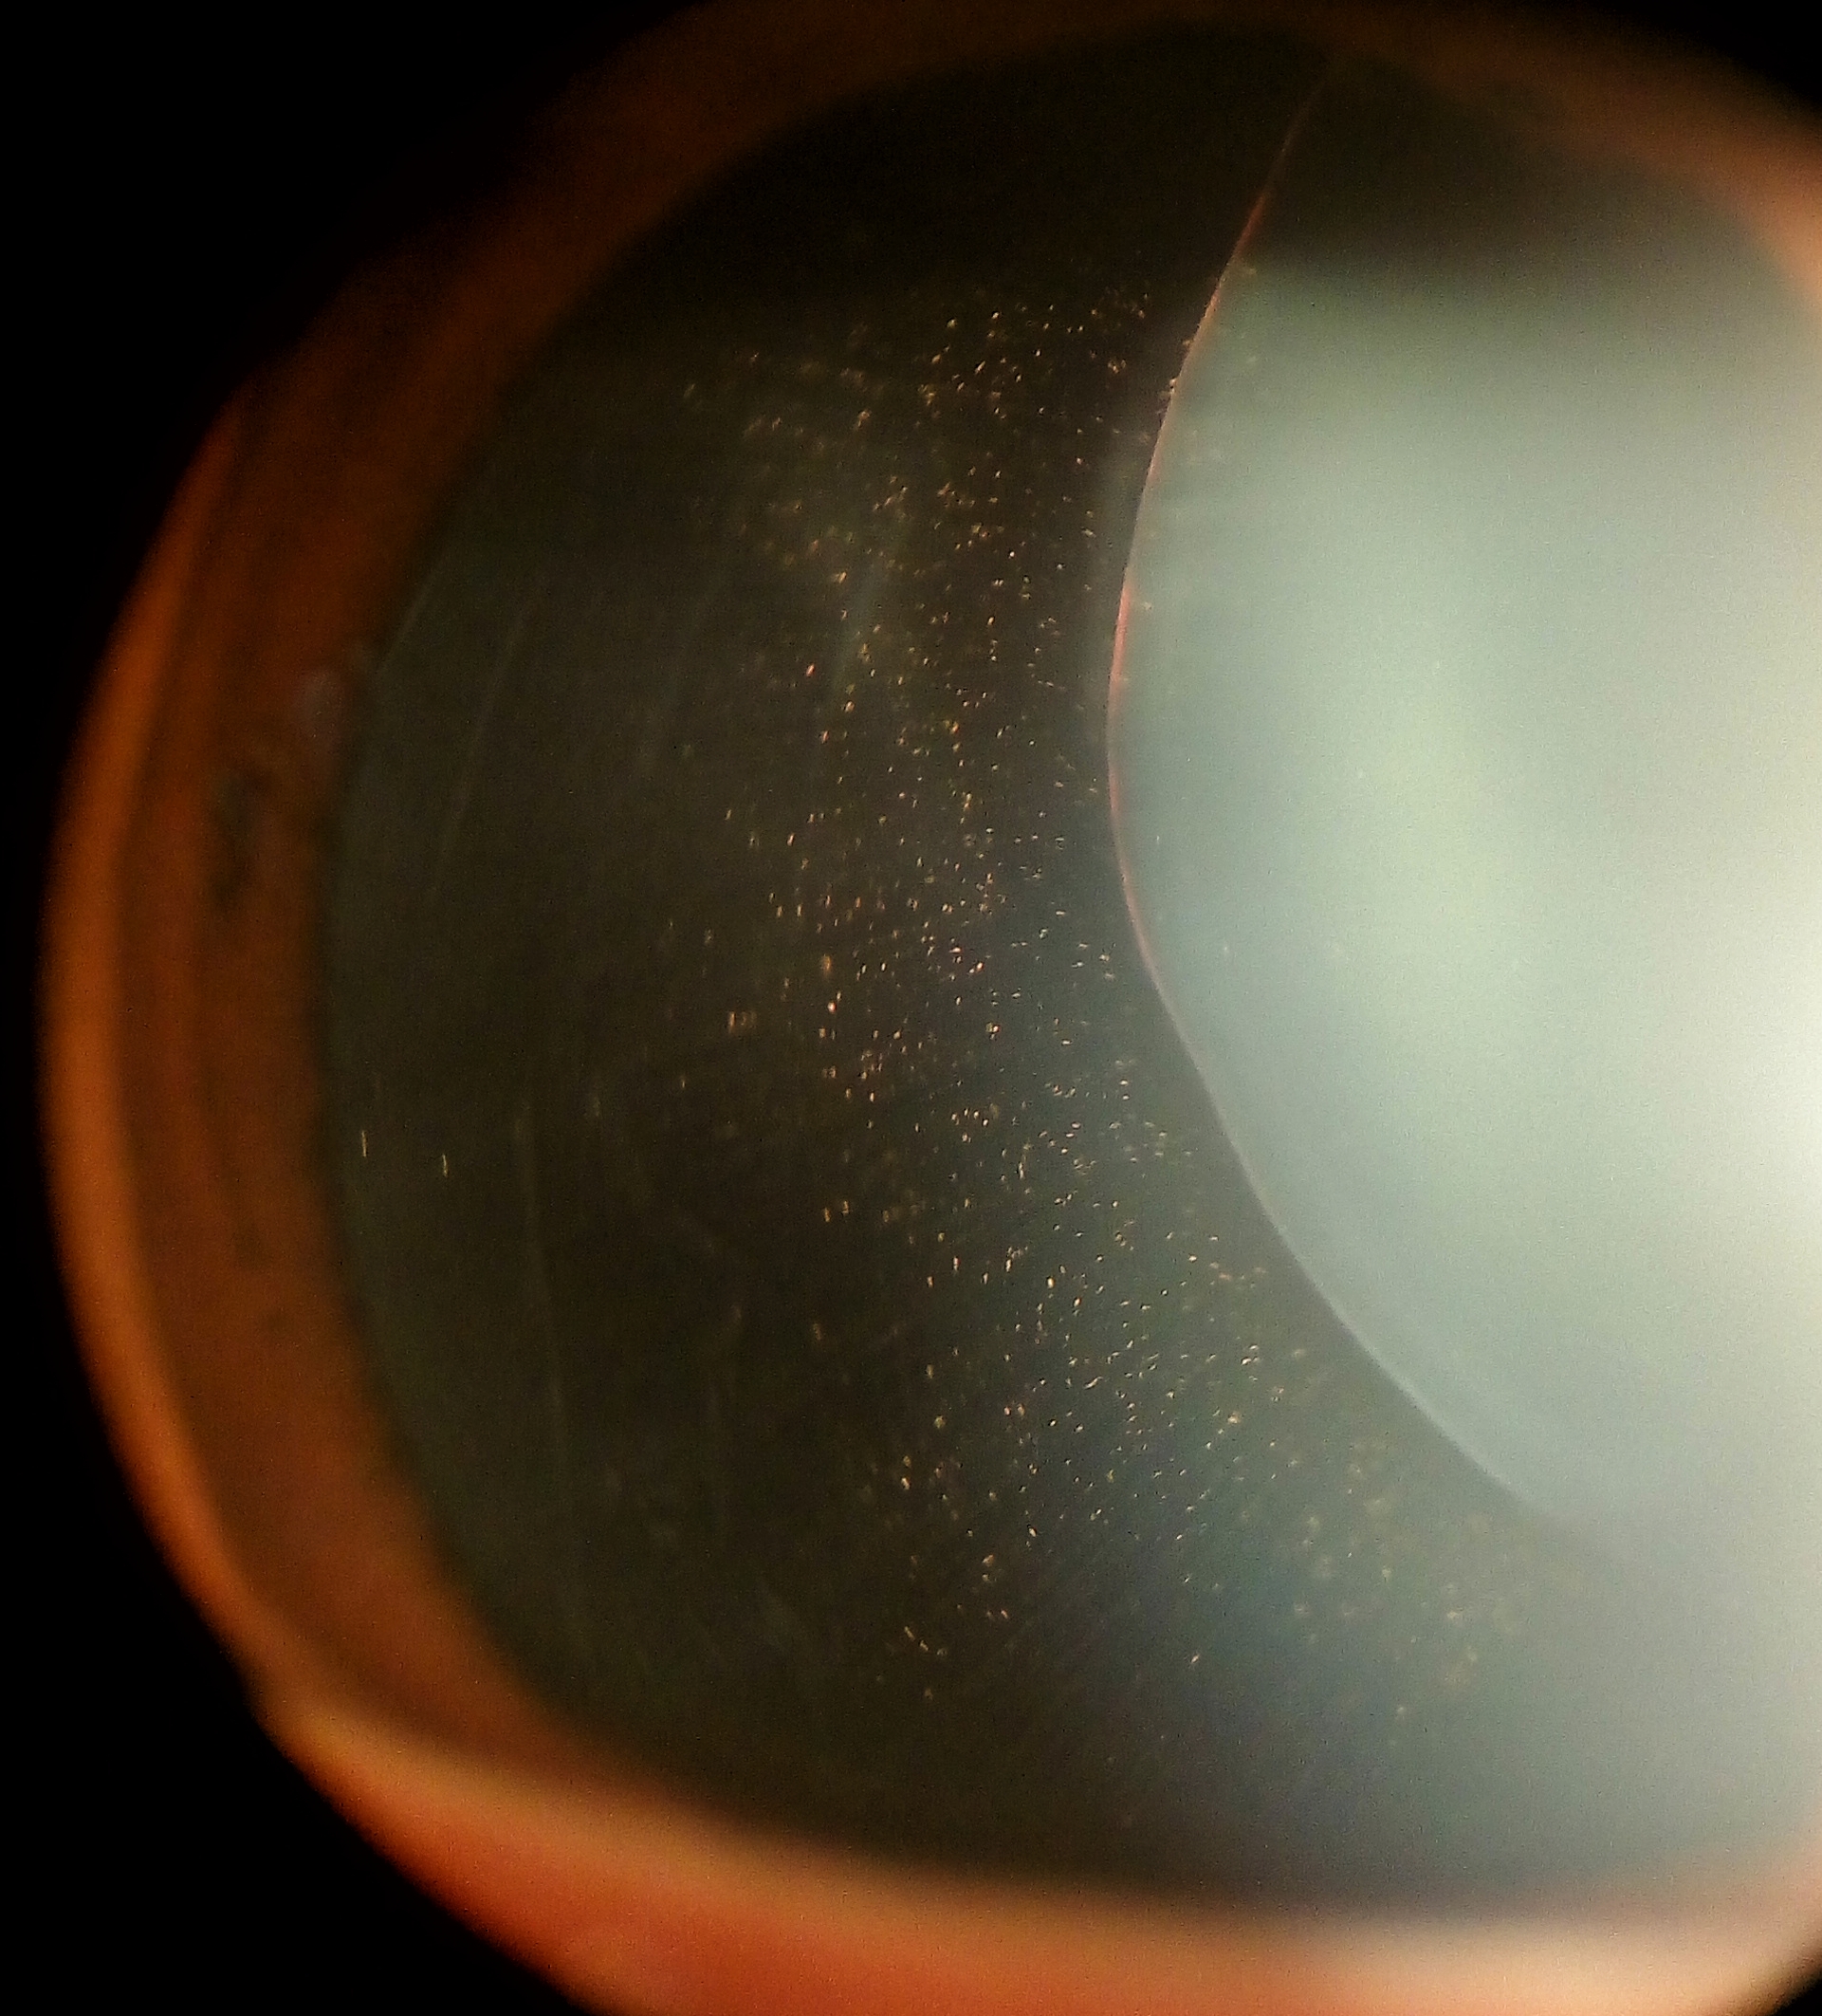

Not surprisingly, MFS represents the systemic disease most commonly associated with ectopia lentis. Classically the lens will dislocate superotemporally, and although any direction of dislocation is theoretically possible, only 20% will dislocate in a non-superior direction. The zonules are often stretched but intact, and iridodonesis and phacodonesis are apparent during slit lamp examination.[14] Pupillary block glaucoma may develop if the lens dislocates into the pupil or anterior chamber. Ectopia lentis is such a strong diagnostic feature of MFS that the diagnosis can be made simply in the presence of ectopia lentis combined with either positive family history of MFS or an enlarged aortic diameter (Z>2). A second major ocular feature of Marfan syndrome is myopia, which accounts for one of the Revised Ghent Nosology systemic features (Table 2). A point is determined by a myopic refraction of greater than 3 diopters. Myopia can be so severe that patients undergoing lens extraction may not require IOL implantation. Uncorrected high refractive error and/or significant anisometropia secondary to lens subluxation occurring in early childhood can contribute to the development of amblyopia.